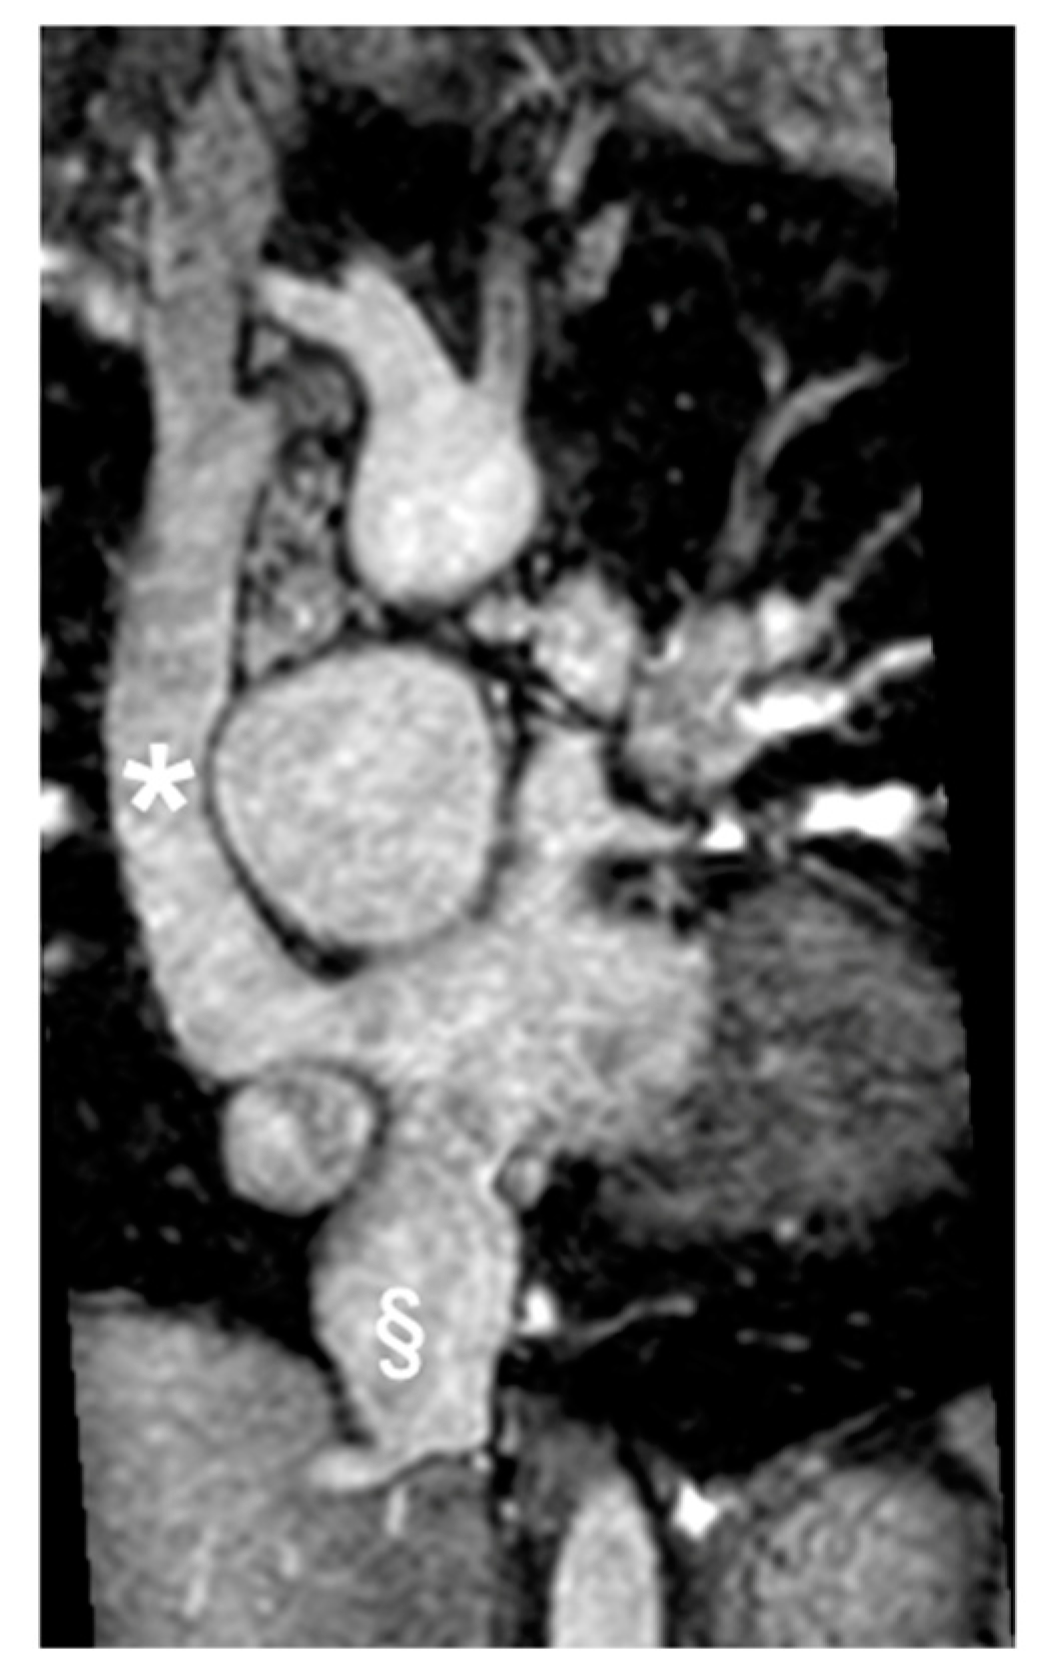

2.3. Coarctation of the Aorta